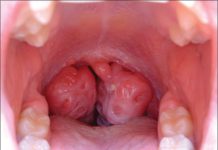

- dolor de garganta con amígdalas hinchadas que pueden tener manchas blancas